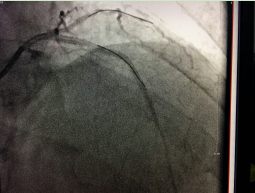

近日,我院成功應(yīng)用切割球囊為一例冠脈內(nèi)支架再狹窄的患者進(jìn)行了冠脈內(nèi)成形術(shù),解除了患者胸悶胸痛癥狀。據(jù)了解,此項(xiàng)技術(shù)的開展在我市市屬醫(yī)院中尚屬首次,該技術(shù)的開展為冠脈支架內(nèi)再發(fā)狹窄的患者帶來福音。??切割球囊???? 老人支架植入后再發(fā)心絞痛 ???冠脈內(nèi)切割球囊成形術(shù)解決難題70多歲的周阿姨兩年前因...